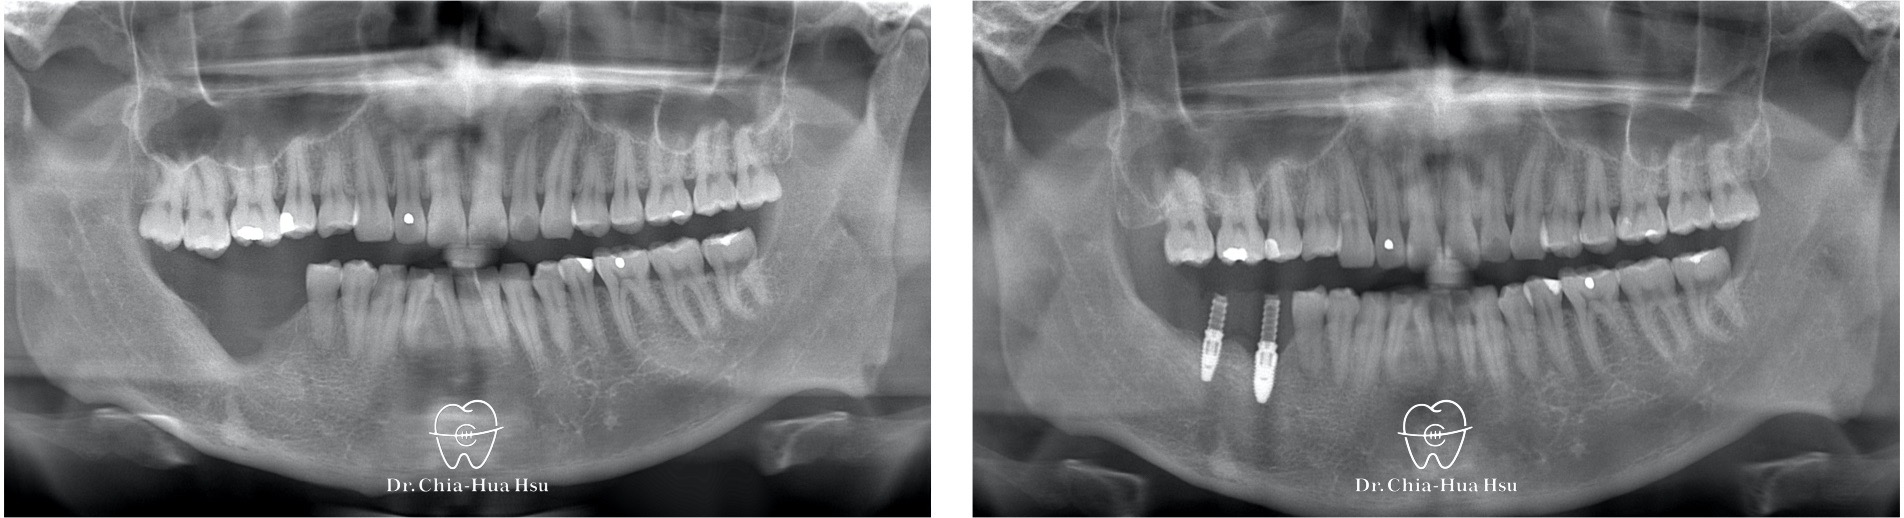

• 病患主訴:有一組用了十幾年的舊牙橋,因為清潔不佳導致牙齒齲齒、假牙鬆。檢查發現齒質不足,因此進行局部矯正評估,看是否能將牙齒拉出來,以便製作新的假牙。

• 問題分析:由於牙齒齒質不足(殘根狀態),為了配合假牙製作,進行局部矯正治療。

治療前

治療後